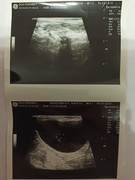

Сделали повторное узи 22.11. 2024 (первое было 09.11.2024). Высылаю фото и заключение.

Теперь ставят гидрометру и эндометрит. По мочевому мочекаменную.